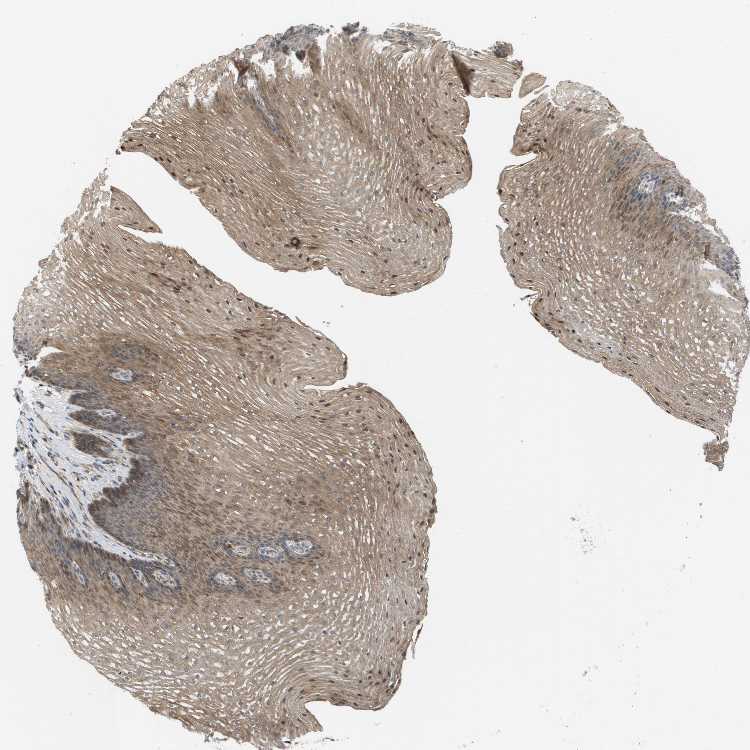

ESOPHAGUS - Antibody stainingi

Antibody staining in the annotated cell types in the current human tissue is reported as not detected, low, medium, or high, based on conventional immunohistochemistry profiling in selected tissues. This score is based on the combination of the staining intensity and fraction of stained cells.

Each image is clickable and will lead to virtual microscopy that enables deeper exploration of all samples and also displays staining intensity scores, fraction scores and subcellular localization as well as patient and tissue information for each sample.

Antibody HPA015696Antibody HPA017343

Squamous epithelial cells MediumMedium